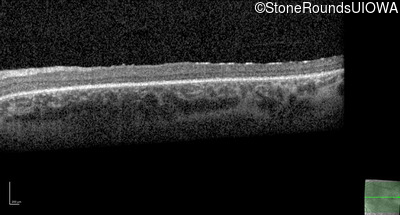

Optical Coherence Tomography - Right - 10/200 -2 sc

Exemplar / OCT Stack